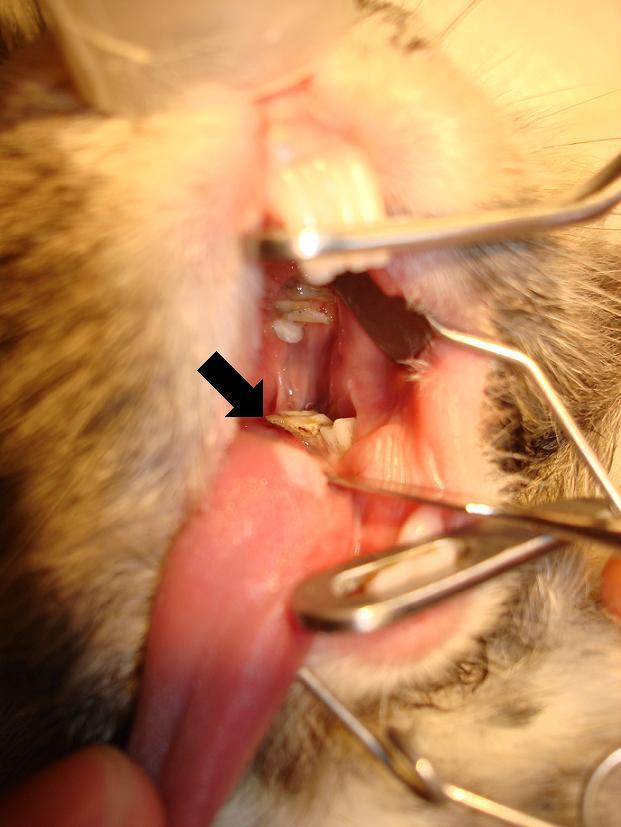

Na fotografiích můžete vidět přerůstání stoliček a formování zubů do špiček zraňujících sliznici jazyka:

Přerůstání zubů u králíků Přerůstání zubů u králíků